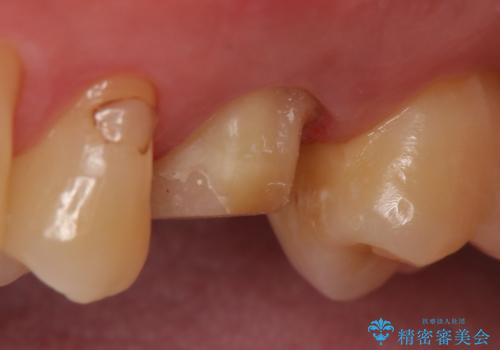

検査の結果歯の神経が死んでいたため根管治療を施し、症状が治まったのを確認後オールセラミッククラウンによる補綴を行いました。

今回用いたオールセラミッククラウンはジルコニアフレームという白い素材の上にセラミックを盛っているため、審美性が非常に高いのが特徴です。

また、ジルコニアは人工ダイヤモンドの材料にも使われているほど高い強度を持っており、そのためオールセラミッククラウンは審美性だけでなく、奥歯やブリッジの補綴も可能とするクラウンです。